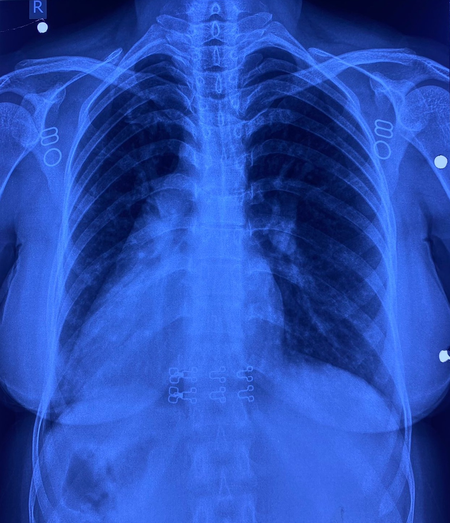

इस मरीज के सभी अंग सामान्य जगह के उलट यानी मिरर इमेज में थे। उसके दिल की जगह दाईं ओर थी, लिवर बाईं ओर, प्लीहा दाईं ओर और पेट भी दाईं ओर था। इसके साथ ही मरीज में जन्मजात आंशिक एट्रियोवेंट्रिकुलर कैनाल दोष जैसी जन्मजात हृदय रोग की समस्या भी थी।

सर्जरी के दौरान चिकित्सा टीम ने अत्यंत सावधानी बरतते हुए मरीज के हृदय दोष का सफल उपचार किया। मात्र 4 सेंटीमीटर के सूक्ष्म ‘इन्फ्रामैमरी’ चीरे के जरिए यह जटिल प्रक्रिया संपन्न की गई। ऑपरेशन के दौरान हृदय की कार्यप्रणाली को सुचारू रखने के लिए शरीर की बाहरी नसों की सहायता से ‘कार्डियोपल्मोनरी बाईपास मशीन’ का उपयोग किया गया। हृदय के दोष को ठीक करने के लिए मरीज की अपनी ‘पेरिकार्डियम’ (हृदय की सुरक्षा झिल्ली) से पैच तैयार किया गया और उसे बेहद बारीक टांकों के जरिए सटीक स्थान पर लगाया गया, ताकि हृदय के वाल्व और कंडक्शन सिस्टम को कोई क्षति न पहुंचे। सर्जरी के बाद मरीज की रिकवरी बहुत ही सहज रही और अब वह अस्पताल से जाने के लिए पूरी तरह फिट है। इकोकार्डियोग्राफी ने भी सफल सर्जरी की पुष्टि की।

इस सर्जरी में कई चुनौतियां थीं। सबसे बड़ी चुनौती यह थी कि जन्मजात हृदय दोष, वाल्व और संवेदनशील कंडक्शन सिस्टम के अत्यंत निकट था। इसके अतिरिक्त, रक्त वाहिकाओं की ‘मिरर इमेज’ (विपरीत दिशा) स्थिति ने सर्जरी को और भी पेचीदा बना दिया था। महज 4 सेंटीमीटर के छोटे चीरे के माध्यम से उपकरणों को संभालना और सूक्ष्म टांके लगाना तकनीकी रूप से बेहद कठिन कार्य था। मरीज को हृदय–फेफड़ों की मशीन के माध्यम से बायपास करना पड़ा, जिससे टीम की विशेषज्ञता और अनुभव की जरूरत थी।

साइटस इन्वर्सस अपने आप में बहुत ही दुर्लभ है और इसके साथ आंशिक एट्रियोवेंट्रिकुलर कैनाल दोष होना और भी कम होता है। आम तौर पर ऐसी सर्जरी में सीने की हड्डी काटनी पड़ती है, लेकिन इस केस में सिर्फ छोटे कॉस्मेटिक चीरे से सर्जरी की गई, जिससे यह दुनिया की पहली सर्जरी बन गई। मरीज रमबाई और उनके परिवार ने डॉ. नरेन्द्र सिंह झाझड़िया और पूरी टीम का दिल से धन्यवाद किया।